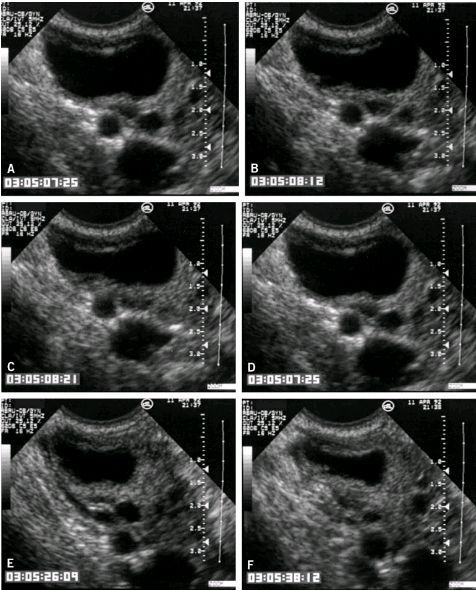

- Подсчет базальных антральных фолликулов (БАФ). В этом тесте техник проводит трансвагинальное УЗИ для подсчета количества мелких фолликулов (киста с яйцеклеткой внутри), доступных для стимуляции в начале цикла лечения.

Что такое тест подсчета антральных фолликулов?

Анализ антральных фолликулов — это трансвагинальное ультразвуковое исследование, при котором измеряется количество имеющихся у вас антральных фолликулов.Ультразвуковой техник или врач использует зонд, вставленный во влагалище, для исследования и подсчета количества антральных фолликулов в яичниках. Это занимает всего несколько минут, подобно гинекологическому осмотру.

Антральные фолликулы очень маленькие — от 2 до 9 миллиметров в диаметре — но их все же можно увидеть на УЗИ.

Количество видимых антральных фолликулов может дать вашему врачу примерное представление о том, сколько всего яйцеклеток (включая множество фолликулов, которые еще слишком малы, чтобы их можно было увидеть) осталось в ваших яичниках.

Хотя его часто проводят на третий день менструального цикла одновременно с другими тестами на фертильность, на самом деле его можно сделать в любое время.

Сколько антральных фолликулов в норме?

Это зависит от вашего возраста. Если вы старше, у вас будет меньше антральных фолликулов, чем у тех, кто моложе. В среднем женщины в возрасте от 20 до 30 лет имеют от 12 до 30 антральных фолликулов, в то время как женщины в возрасте от 35 до 40 лет могут иметь от 8 до 15, а женщины в возрасте от 41 до 46 лет могут иметь от четырех до 10.

Сколько незрелых фолликулов указывает на синдром поликистозных яичников (СПКЯ)?

У женщин с СПКЯ больше антральных фолликулов, чем у женщин без СПКЯ. У женщины с СПКЯ нередко бывает более 30 антральных фолликулов.